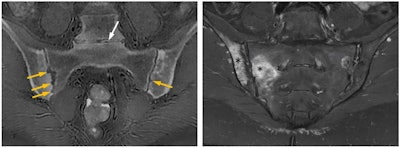

ZTE is an MRI sequence that visualizes tissues such as bone with the shortest T2 values giving images with a CT-like appearance, Prince explained. Signal is acquired immediately after applying the radiofrequency pulse, resulting in a near zero echo time, with the next radiofrequency pulse following in a very short repetition time.

In theory, zero echo time could help to visualize MR imaging of any joint, according to Prince. ZTE sequences are resilient to artifacts caused by motion and magnetic field homogeneities, with great signal-to-noise ratio and scan time efficiencies, and they have advantages in depicting small bone fragments in a trauma setting and subtle cortical erosion.

"ZTE may remove the need for CT, with detailed depiction of bone anatomy, making an MRI examination a one-stop imaging examination for conditions such as femoroacetabular impingement, giving both soft tissue and bone imaging within the same examination," she noted. "Substantial agreement is being found in morphometric analyses, with reproducibility of many lytic or sclerotic lesions -- although spatial resolution is still inferior to CT or radiography."

It has shown value in bone morphology, assessment of fractures, displaced bone fragments, shoulder instability, calcification (ossification of ligaments, calcific tendinitis) spinal foramina stenosis, skull assessment (suture closure, trauma), and assessment of bone erosions in bone tumors, Prince added. It may also demonstrate a wide range of structural abnormalities and disease or healing processes.